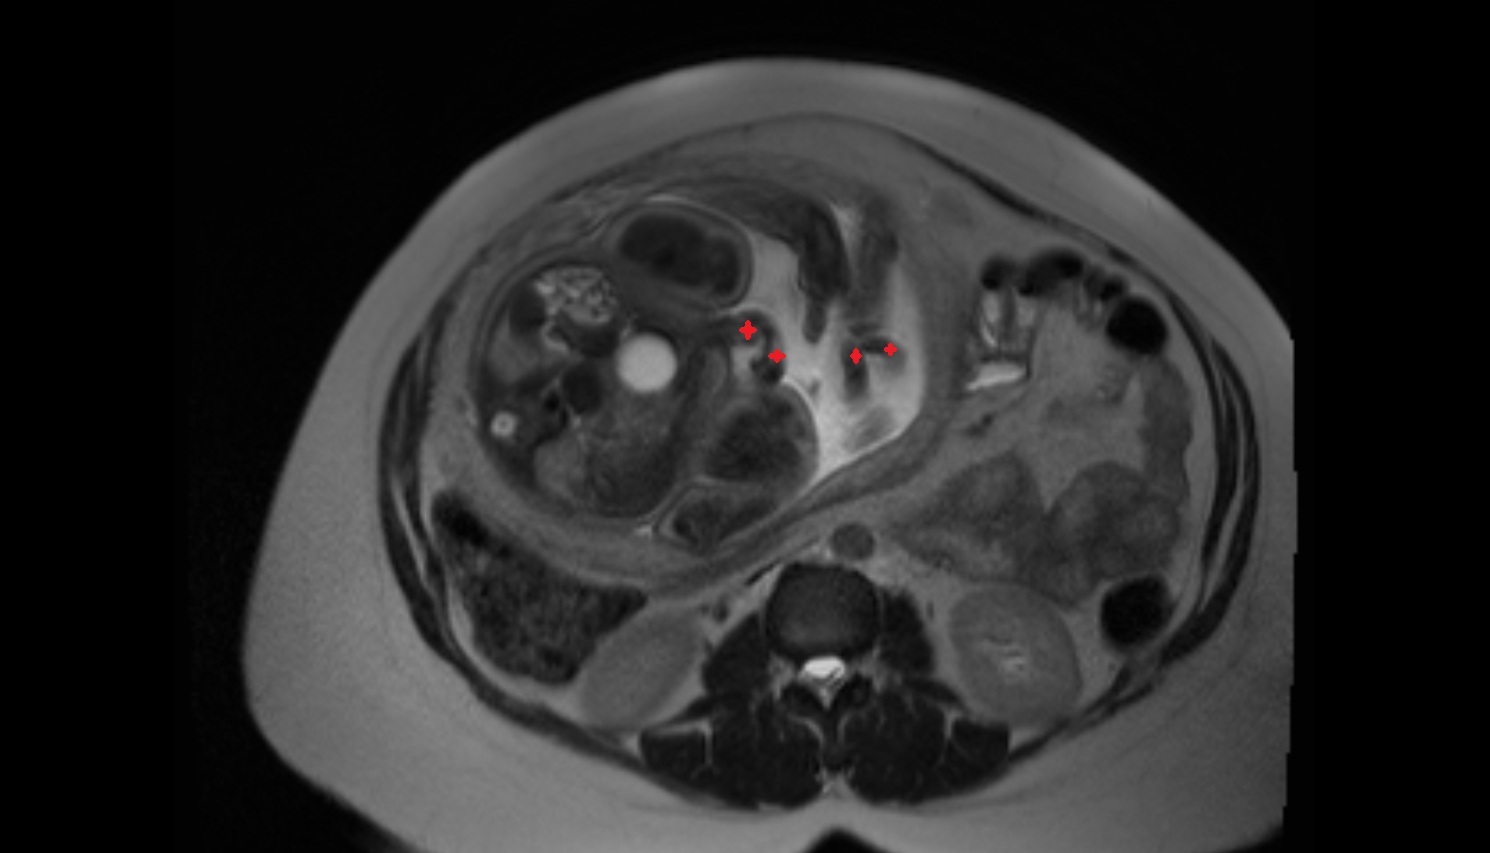

- Placenta

- Uterus (pregnancy)

- Amniotic fluid

- Umbilical cord

- Fetal brain

- Fetal caudate nucleus

- Fetal thalamus

- Fetal Heart

- Fetal Liver

- Fetal kidneys